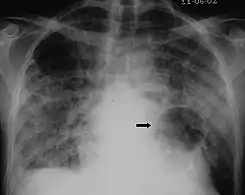

The diagnosis can be confirmed by the characteristic appearance of the chest X-ray and an arterial oxygen level (PaO2) that is strikingly lower than would be expected from symptoms. Gallium 67 scans are also useful in the diagnosis. They are abnormal in about 90% of cases and are often positive before the chest X-ray becomes abnormal. Chest X-ray typically shows widespread pulmonary infiltrates. CT scan may show pulmonary cysts (not to be confused with the cyst-forms of the pathogen).

Chest X-ray of increased opacification (whiteness) in the lower lungs.

These chest radiographs are of two patients. Both show ground glass opacities. The left X-ray shows a much more subtle ground-glass appearance while the right X-ray shows a much more gross ground-glass appearance mimicking pulmonary edema.[7]

X-ray of a cyst in pneumocystis pneumonia[7]